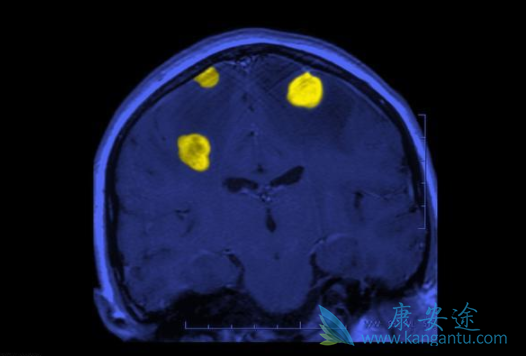

治疗应去除病因,再对症处理,一旦经影像学确诊发生RPLS,应立即停药,再给予降压等对症治疗,一般会在数天内好转,此病预后良好。进行性多灶性白质脑病(PML)是一种亚急性脱髓鞘性疾病,常见于免疫系统功能受到严重抑制的患者,最常出现的症状为视觉障碍、肌无力和认知功能的改变,其致死率高,大部分患者在发病后3-6个月内死亡。

进行性多灶性白质脑病的发病率虽然较低,但由于其病情进展迅速,且目前尚无可靠的预防措施及有效的治疗方法,患者的预后往往极差。在利妥昔单抗的治疗过程中,如果患者出现神经症状,应考虑请神经科医师会诊,并进行相关检查。对于确诊为PML的患者,应停止使用利妥昔单抗,同时采取积极的抗病毒治疗,以尽早重建机体免疫系统。